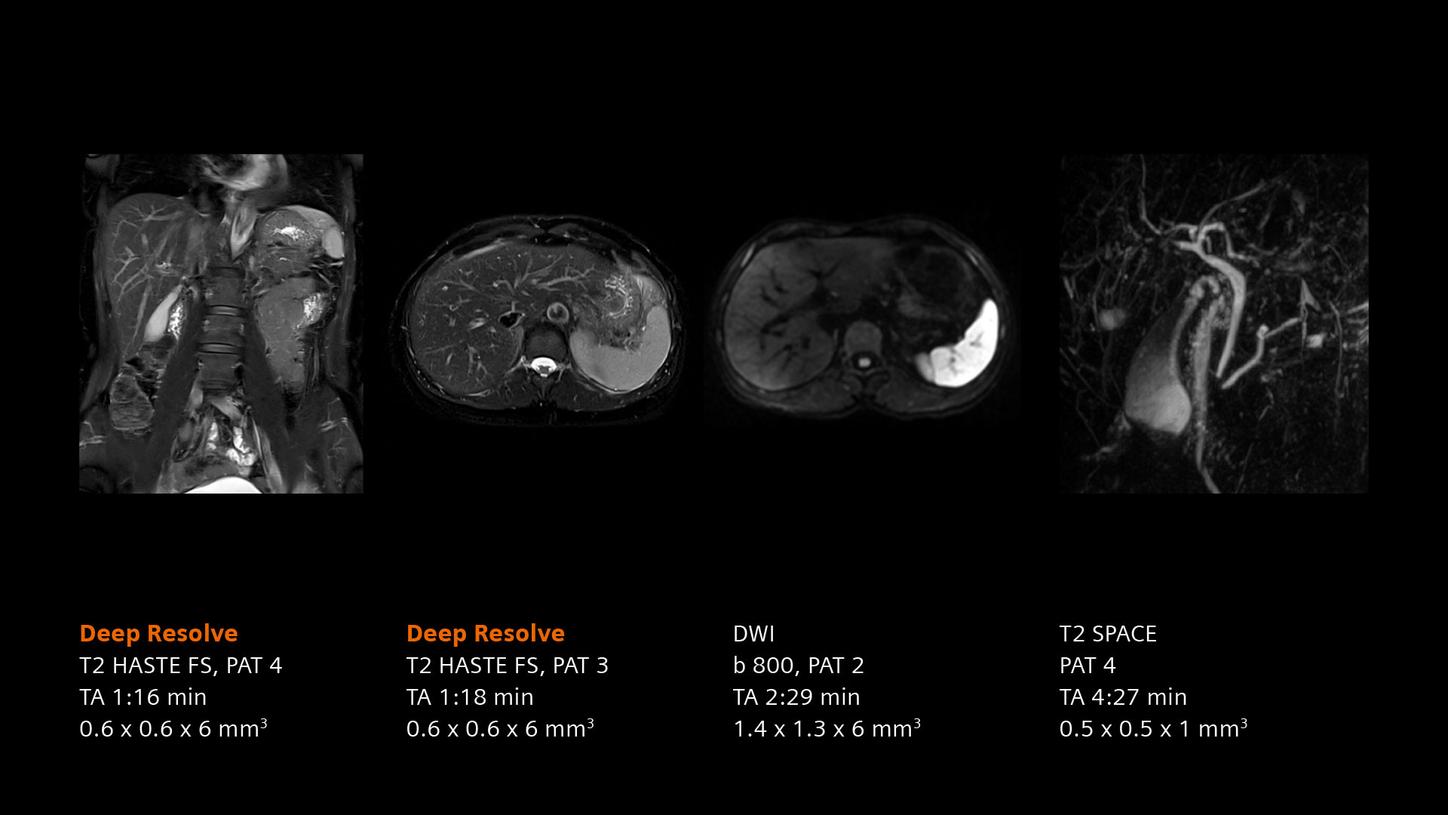

Deep Resolve will be at the forefront of the revolution in MRI acceleration. Deep Resolve will enable our fastest MRI, with images that will have extraordinary clarity, higher clinical productivity, and an even better patient experience. This transformational effect of Deep Resolve is now planned to expand to 3D5, unlocking a new dimension in MRI image resolution and speed.